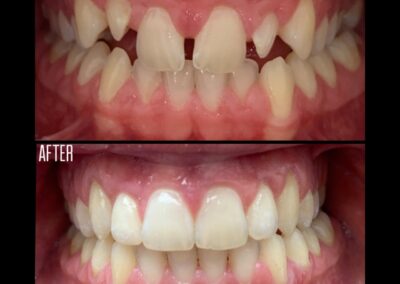

Gallery